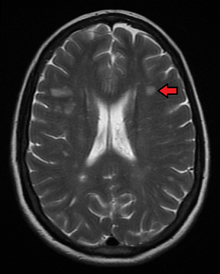

The name multiple sclerosis refers to the scars (sclerae – better known as plaques or lesions) that form in the nervous system. These lesions most commonly affect the white matter in the optic nerve, brain stem, basal ganglia, and spinal cord, or white matter tracts close to the lateral ventricles.[2] The function of white matter cells is to carry signals between grey matter areas, where the processing is done, and the rest of the body. The peripheral nervous system is rarely involved.[3]

To be specific, MS involves the loss of oligodendrocytes, the cells responsible for creating and maintaining a fatty layer—known as the myelin sheath—which helps the neurons carry electrical signals (action potentials).[2] This results in a thinning or complete loss of myelin and, as the disease advances, the breakdown of the axons of neurons. When the myelin is lost, a neuron can no longer effectively conduct electrical signals.[3] A repair process, called remyelination, takes place in early phases of the disease, but the oligodendrocytes are unable to completely rebuild the cell's myelin sheath.[41] Repeated attacks lead to successively less effective remyelinations, until a scar-like plaque is built up around the damaged axons.[41] These scars are the origin of the symptoms and during an attack magnetic resonance imaging (MRI) often shows more than ten new plaques.[2] This could indicate that there are a number of lesions below which the brain is capable of repairing itself without producing noticeable consequences.[2] Another process involved in the creation of lesions is an abnormal increase in the number of astrocytes due to the destruction of nearby neurons.[2] A number of lesion patterns have been described.[42]

Clinical data alone may be sufficient for a diagnosis of MS if an individual has had separate episodes of neurological symptoms characteristic of the disease.[46] In those who seek medical attention after only one attack, other testing is needed for the diagnosis. The most commonly used diagnostic tools are neuroimaging, analysis of cerebrospinal fluid and evoked potentials. Magnetic resonance imaging of the brain and spine may show areas of demyelination (lesions or plaques). Gadolinium can be administered intravenously as a contrast agent to highlight active plaques and, by elimination, demonstrate the existence of historical lesions not associated with symptoms at the moment of the evaluation.[46][48] Testing of cerebrospinal fluid obtained from a lumbar puncture can provide evidence of chronic inflammation in the central nervous system. The cerebrospinal fluid is tested for oligoclonal bands of IgG on electrophoresis, which are inflammation markers found in 75–85% of people with MS.[46][49] The nervous system in MS may respond less actively to stimulation of the optic nerve and sensory nerves due to demyelination of such pathways. These brain responses can be examined using visual- and sensory-evoked potentials.[50]